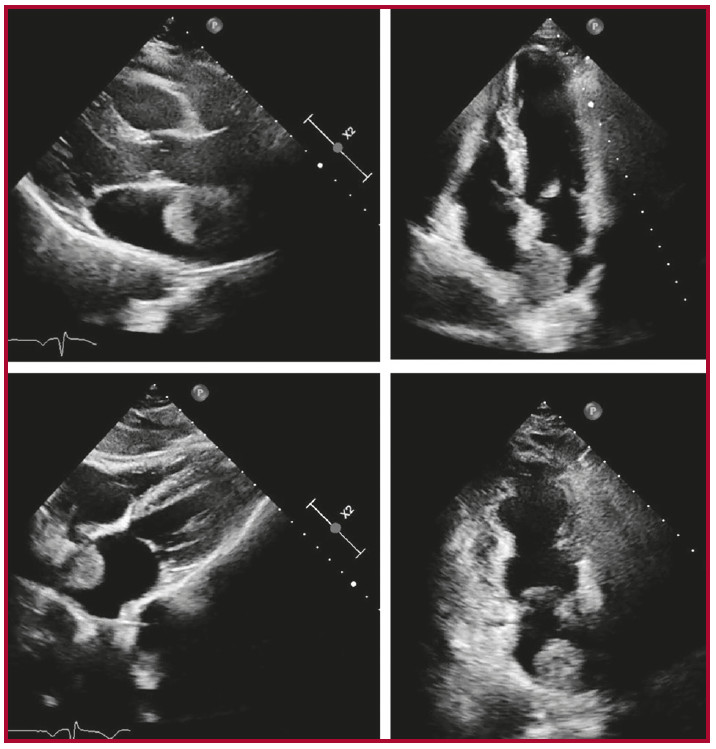

Se prosigue con la realización de un ecocardiograma Doppler que evidencia imagen heterogénea redondeada en la aurícula izquierda, adherida al septum interauricular, sésil, con amplio movimiento anárquico, en contacto con la vena pulmonar superior derecha sin invadirla. Dicha imagen no interfiere con la apertura y cierre de la válvula mitral (Figura 2).